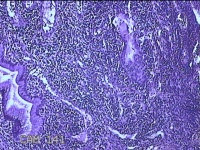

宫颈赘生物

性别

女

年龄

42岁

临床诊断

宫颈赘生物待查?

一般病史

阴道不规则流血15天。

标本名称

大体所见

灰白暗红色肿物1.3x0.7x0.3cm一个,表面糜烂。

图1